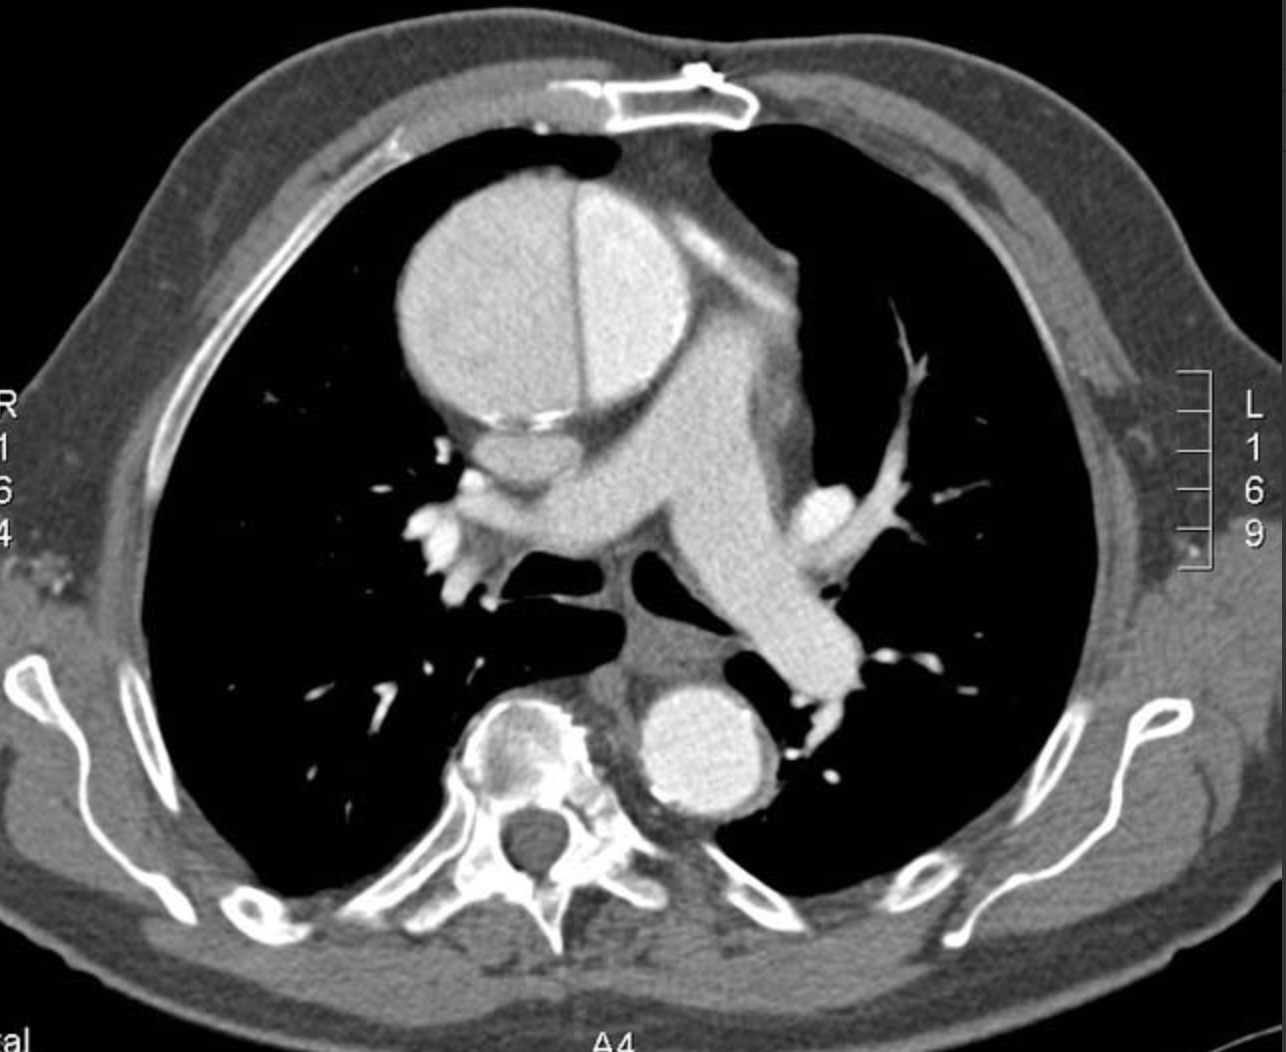

What type of aortic dissection can be seen on this image?

A

Type A

Can see flap in the ascending aorta